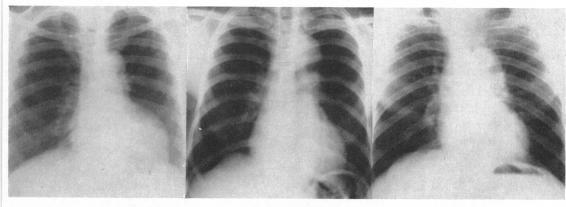

Dilatation and unfolding of the aorta in a Jamaican population.

Br Heart J. 1962 Jul;24(4):455-63. doi: 10.1136/hrt.24.4.455.